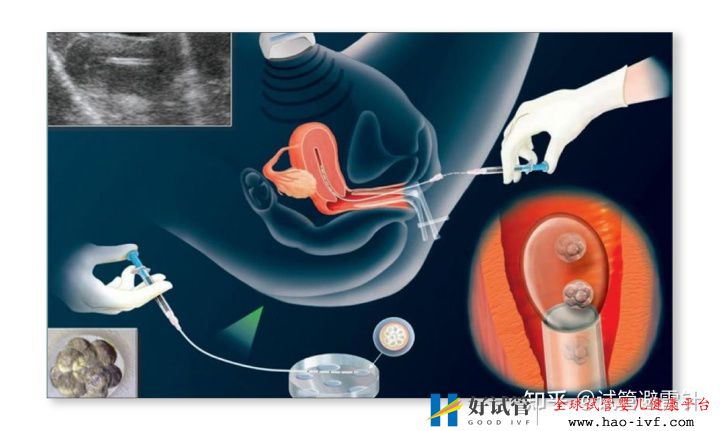

试管婴儿费用大约多少2021年——3.国内一二代试管婴儿费用详解试管婴儿费用大约多少2021年:国内试管之(6)胚胎移植

胚胎移植是将受精卵子移植到子宫内的过程,一般在取卵后第4天,整个过程其实没什么感觉,但移植后,要尽可能地平躺48小时以上,除了必要的上厕所外,基本都躺在床上。有些患者比较谨慎,躺在床上超过72小时都有。

这块总费用:

1. 移植的手术费用,大概一千五百;2. 如果冷冻胚胎需要做复苏,费用大概是三千块;3. 如果第一次移植失败,第二次的复苏费用,加上移植费用和胚胎冷冻费用(每年一千五)

总的费用大概到一千五百块,或第二次做移植的六千块。